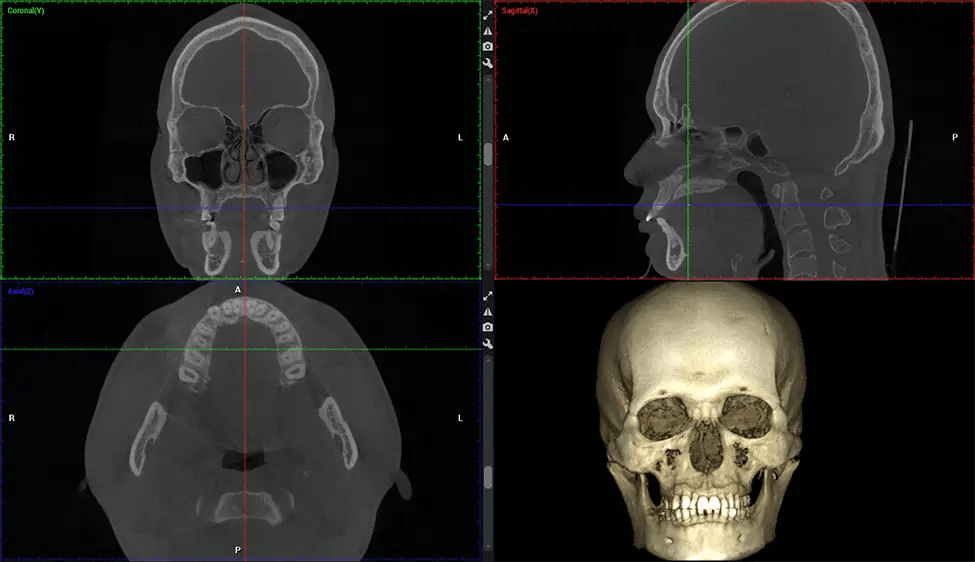

This 3D scan, called cone beam computed tomography, gives your dentist a more complete image of your oral anatomy and disease processes than a traditional X-ray. Unlike conventional X-rays, which capture a 2D image of your mouth from various angles, a 3D scan takes multiple digital X-rays for one image. It provides a complete view of your jaw, teeth, nerves, and soft tissues. This enhanced view allows dentists to detect minor issues not visible in traditional 2D scans, such as impacted wisdom teeth or bone fractures in the sinus cavity.

There are many benefits to using CBCT technology, especially compared to the traditional 2D X-ray format. One of the most significant advantages of CBCT scans is that they provide much more information than traditional X-rays. A scan lets your dentist see images from all angles of your jaw and mouth, including your sinuses, nasal cavity, cheekbones, and other surrounding areas. This added information helps your dentist craft a comprehensive treatment plan that addresses all aspects of your oral health.

Another significant benefit is that 3D imaging provides more precise images of your bone structure. These images are more detailed, providing you with a more accurate diagnosis. An accurate diagnosis means better treatment for you.

After the scanning process, the captured X-ray images are processed by the CBCT software, which applies algorithms to reconstruct a detailed 3D image of the scanned area. The software compiles these individual X-ray images and creates a digital 3D representation of the patient’s anatomy. The reconstructed 3D CBCT image can be viewed and analyzed by the dentist or radiologist. This image can be manipulated, rotated, and zoomed in or out to examine specific structures and evaluate the patient’s condition.

Planmeca Viso G7 CBCT ( Cone Beam CT Scan ) is designed to surpass the demands of industry leaders, specialists, and large institutions. It’s has a large ø25×30 cm sensor with four built-in cameras. It can capture unlimited volume sizes from a ø3×3 cm to a ø30x30cm volume capturing the skullcap through C7 on the cervical spine. The Planmeca Viso G7 offers the industry’s largest single volume scan of ø30×19 cm. It’s poised to handle advanced imaging modalities such as Planmeca ProFace® and Planmeca 4D™ Jaw Motion technology. The occipital head support allows an unimpeded view of facial tissue.